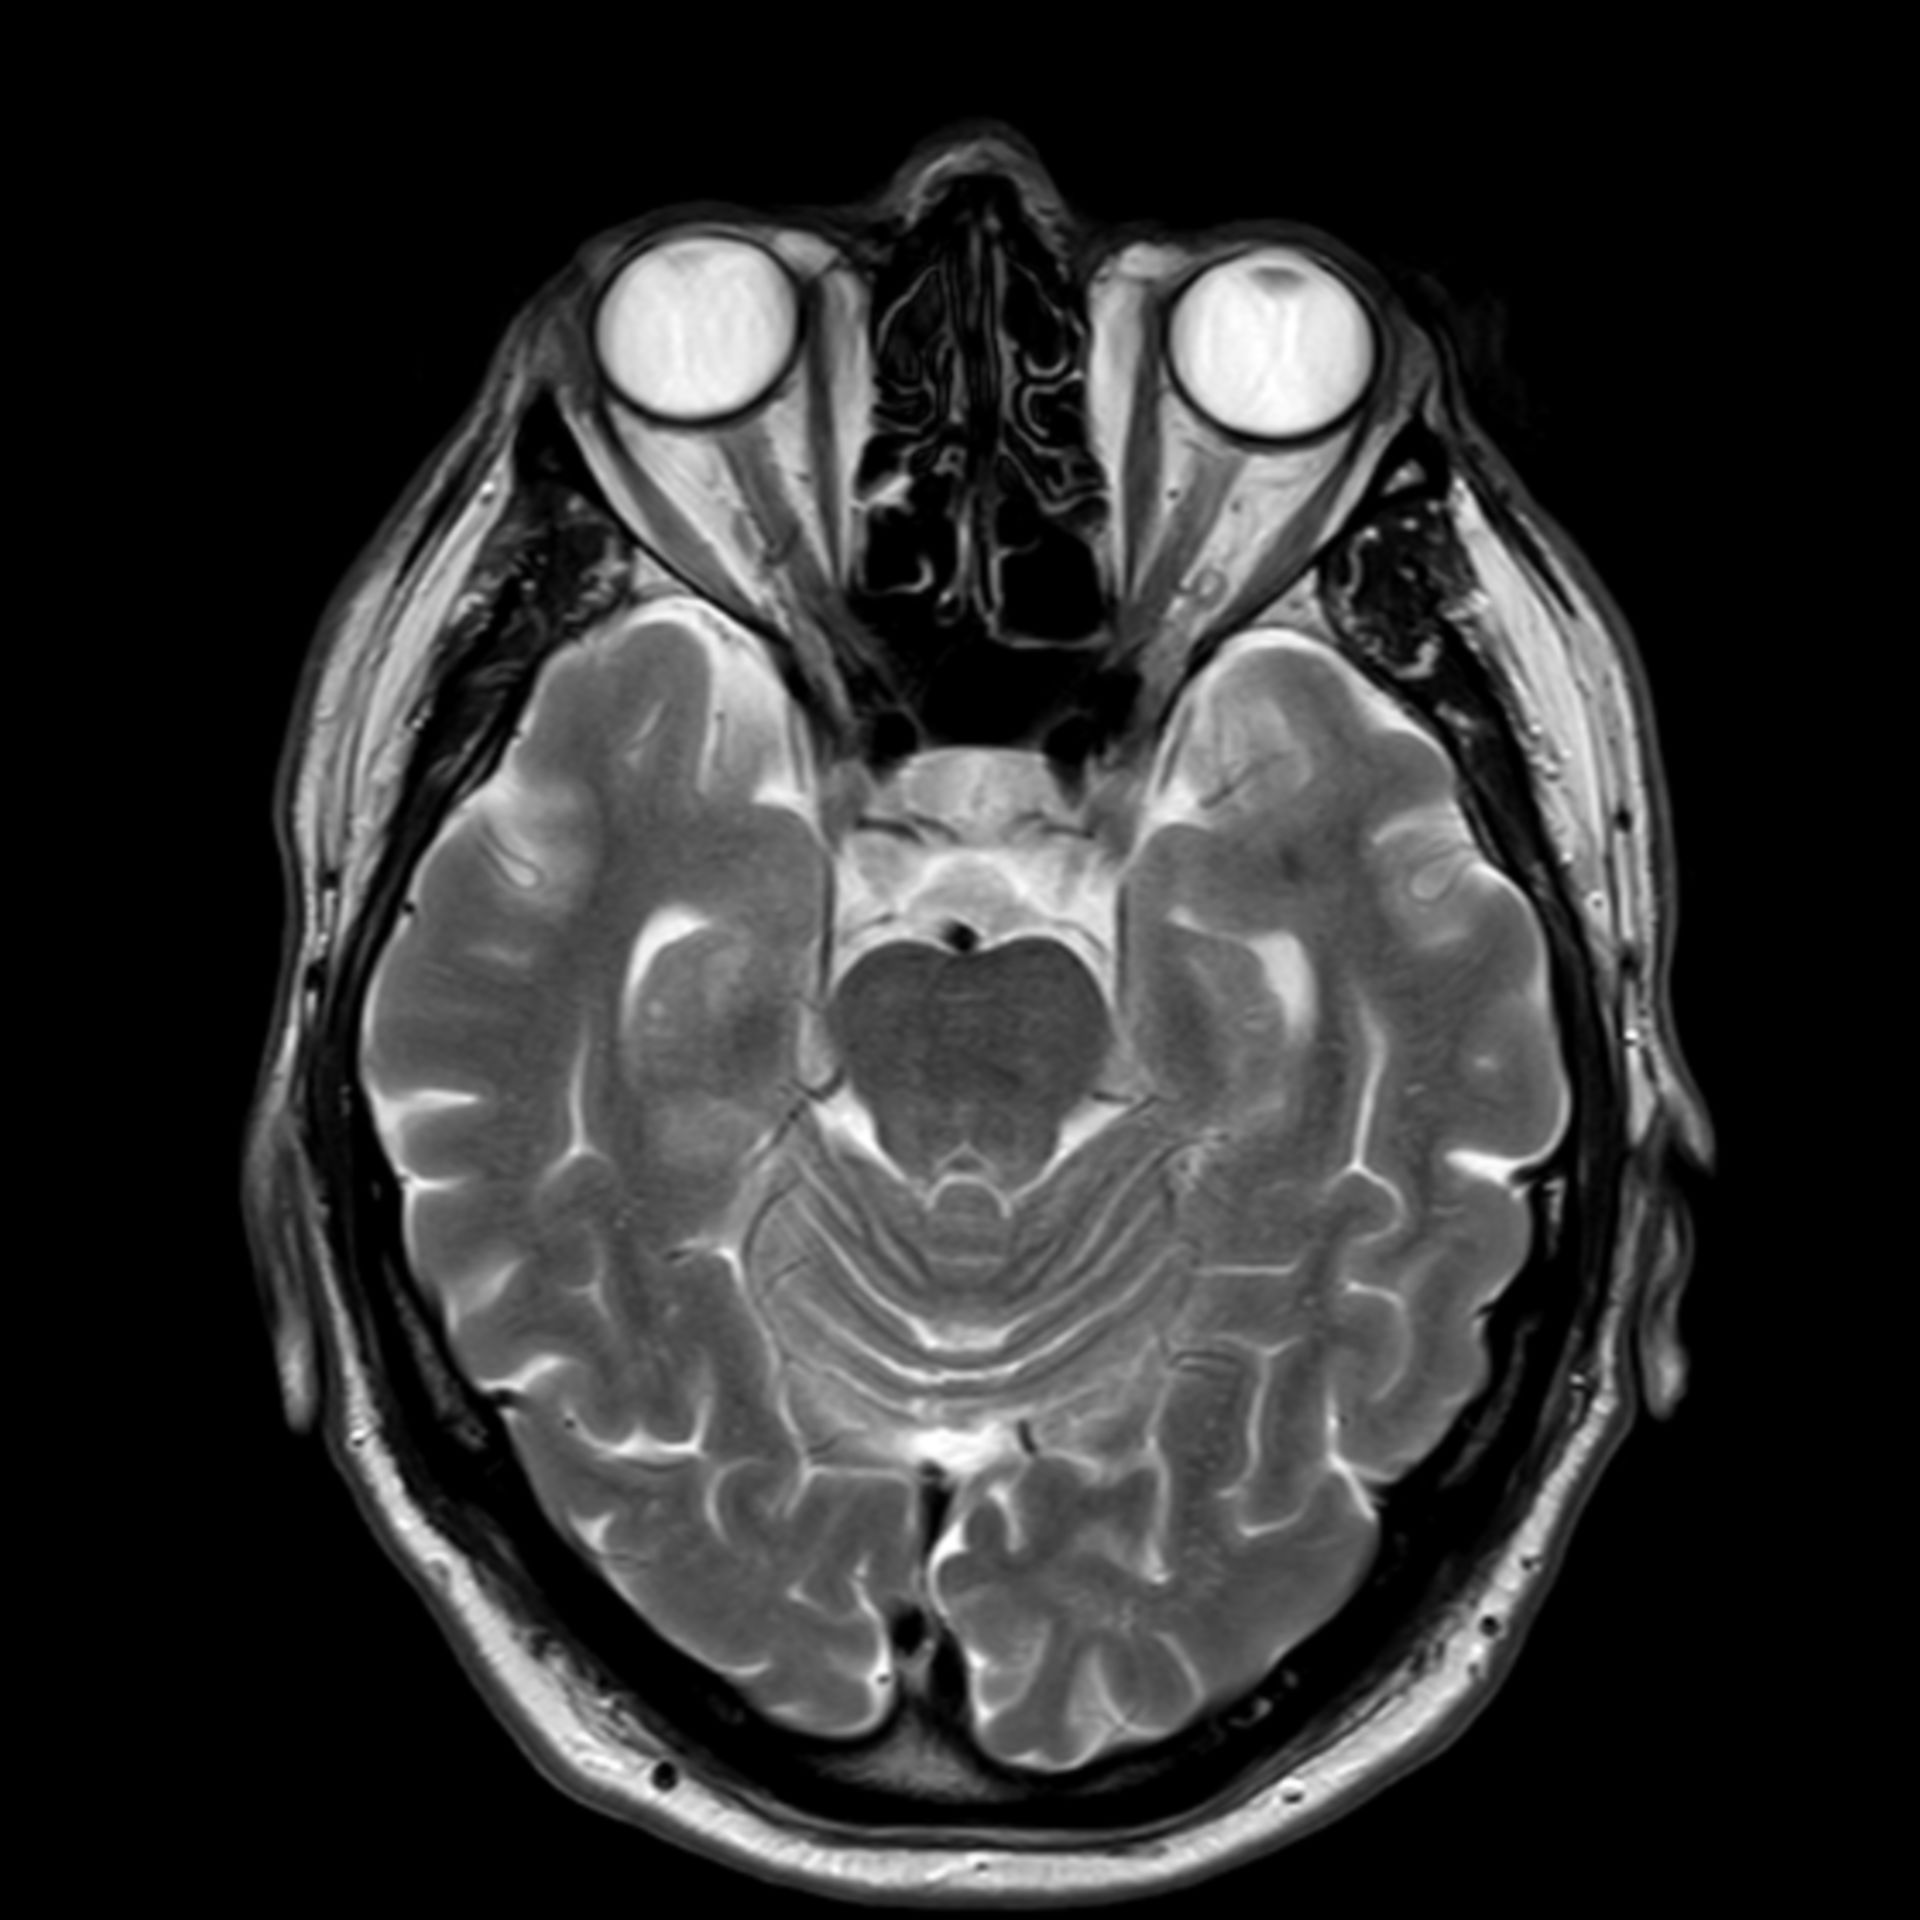

Mrt : Kuala Lumpur’s New MRT Map Alignment. ~ .: Property … / Support more model(qualcomm and … Retinoblastom (MRT/T2) – DocCheck

Retinoblastom (MRT/T1) – DocCheck (11/26) MRT Schädel in Transversalebene, T₁‐gewichtet, FFE – DocCheck

(11/26) MRT Schädel in Transversalebene, T₁‐gewichtet, FFE – DocCheck MS Herd MRT (1) – DocCheck

Retinoblastom (MRT/T2) – DocCheck MRT: Posterior-Hirninfarkt – DocCheck

(16/26) MRT Schädel in Transversalebene, T₁‐gewichtet, FFE – DocCheck MRT Knie – DocCheck

MRT Schädel – DocCheck MRT Bild, könnte das ein Tumor sein? Kennt sich jemand damit aus? Könnte die helle Fläche ein …

MRT Schädel – DocCheck Sichere Prostatavorsorge mittels MRT-Untersuchung der Prostata

MRT Schädel – DocCheck #MRT: Sungai Buloh – Kajang Line Phase 1 To Officially Start 16th December – Hype Malaysia

MRT 4 Schädel – DocCheck Taipei MRT Roadmap